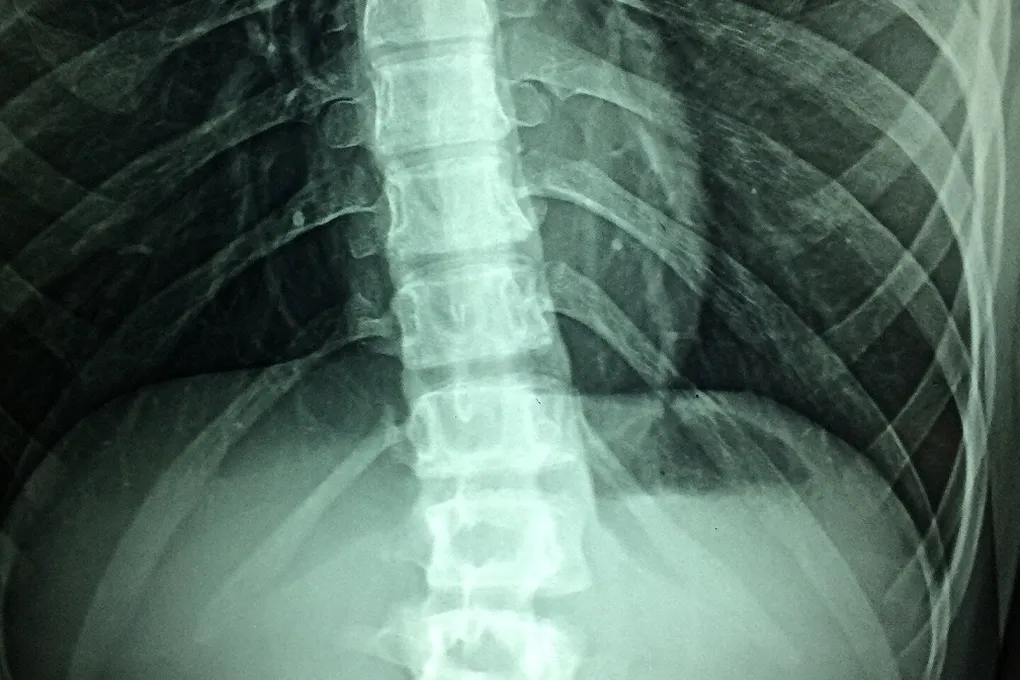

Визуализация регенерирующих проекций из нижнегрудного отдела спинного мозга, которые проецируются на центры выполнения ходьбы, в цельном спинном мозге. EPFL / Neurorestore